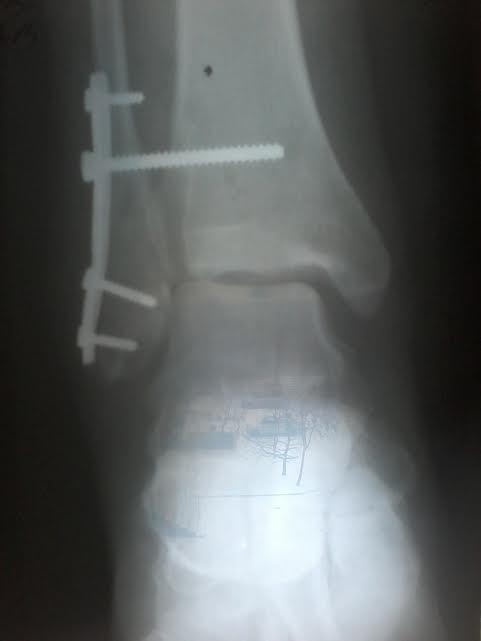

Здравствуйте, 1,5 месяца назад проведен остеосинтез по поводу перелома малоберцовой кости с разрывом синдесмоза. Сделан контрольный снимок. Подскажите пожалуйста, насколько все серьезно, и что делать дальше?

Остается заметный наружный подвывих стопы. Надо сделать сравнительные рентгенограммы обоих голеностопных суставов. Возможно, КТ. Вероятно, понадобится реостеосинтез.